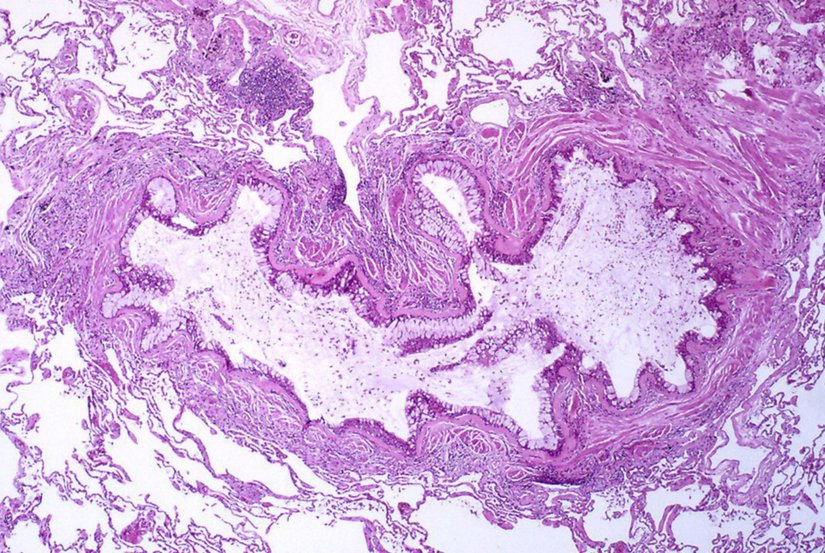

Trakeal ve Bronş Lezyonları

Çeşitli hava yolu tümörlerinin astıma benzer semptomlarla kendini gösterdiği rapor edilmiştir. Bu tümörler, aşağıdaki resimlerde gösterildiği gibi endobronşiyal karsinoid ve mukoepidermoid tümörleri içerir. Bir vakada, sol akciğerinde hiperlüsensi olan 14 yaşındaki bir erkek çocuğunun nihayetinde sol ana bronşta bronşiyal karsinoid olduğu bulundu.[119]